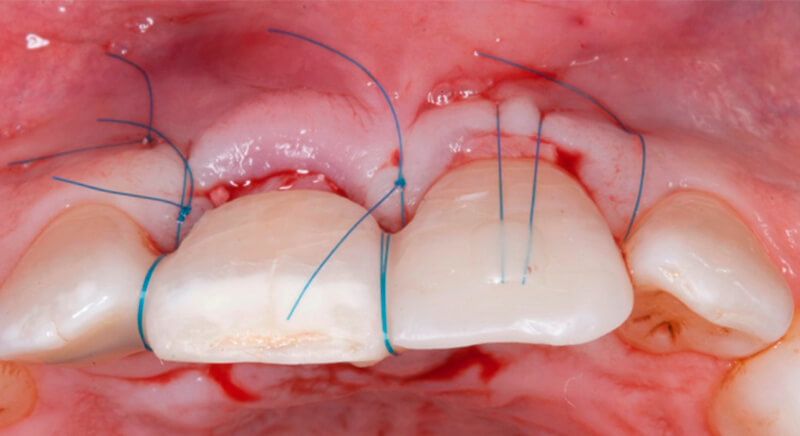

Once the hard and soft tissues had healed, 6 months after the surgery, a good volume remained in the vestibular area. It was then that we could consider an implant, using guided surgery to ensure it was placed in the correct three-dimensional position.

The guided surgery was performed by lifting a full thickness mucoperiosteal flap. A Biomimetic Ocean CC implant, diameter 3.5mm and length 10mm, was inserted using the surgical guide in the ideal three-dimensional position and the defects were regenerated with xenograft and reabsorbable membrane, the nasopalatine duct on the palatine side and the area of dehiscence on the vestibular.

During the same surgical intervention, a short 3mm Avinent healing abutment was positioned and fully covered by the flap. Primary closure was completed and we waited 6 months for the bone graft to mature.